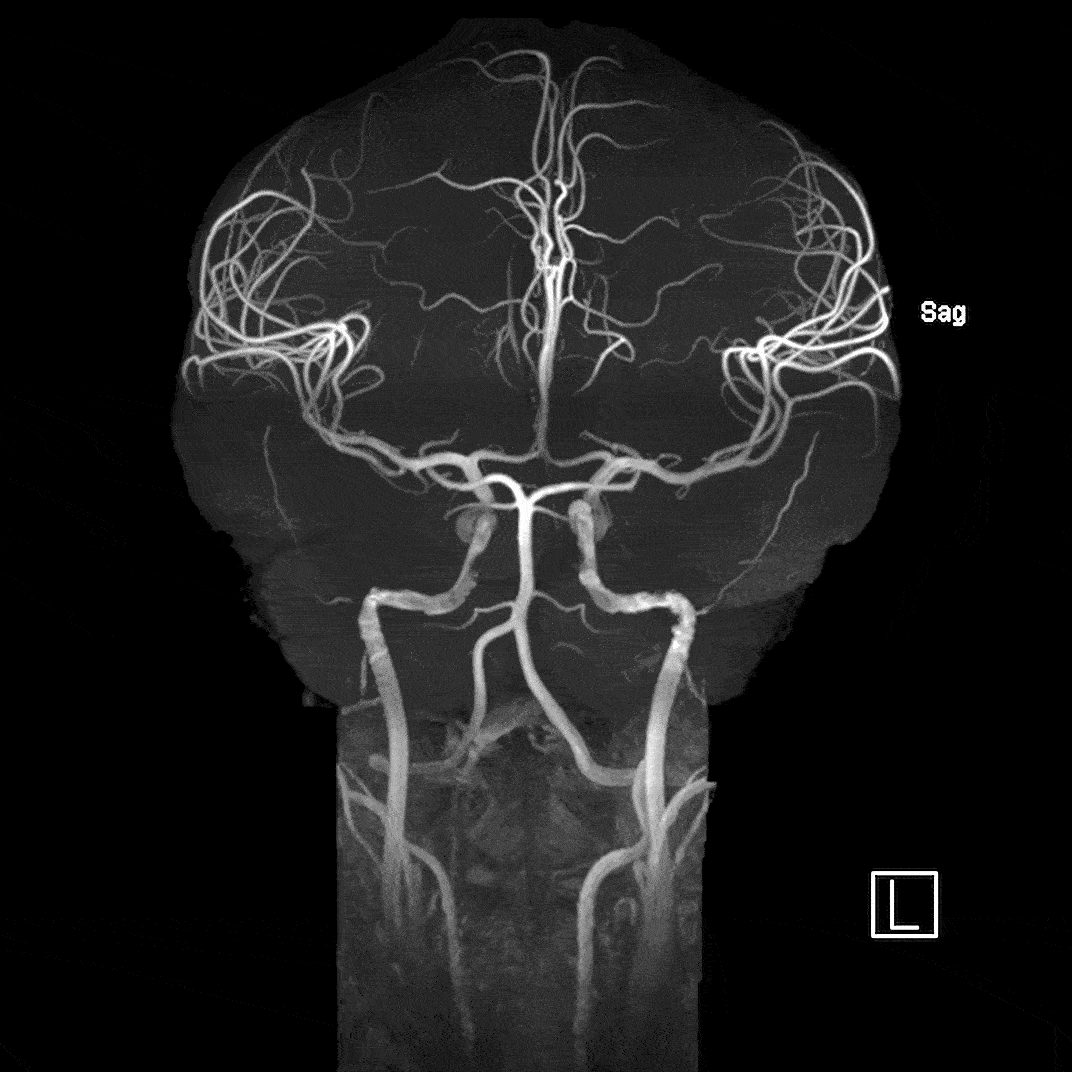

Magnetic Resonance Angiography

Magnetic resonance angiography (MRA) highlights flowing blood to detect issues such as aneurysms, narrowed arteries, blood clots, and other blockages. We use Time of Flight imaging to derive the contrast needed to properly visualize the arterioles.

Imaging parameters

- 0.38 mm isotropic resolution, TE=4.5ms, TR=14ms, acquisition time = 11:37 min